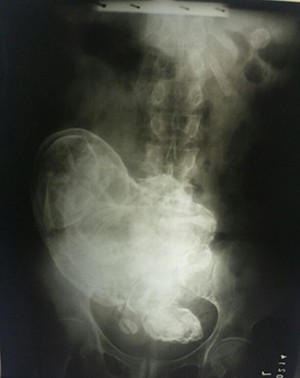

Idosa descobre que carrega feto morto no abdômen há 44 anos Segundo a ginecologista, o corpo da idosa encontrou uma forma de conviver com o feto. (Foto: Divulgação).

Uma idosa de 84 anos descobriu que carrega um feto no abdômen há 44 anos. O caso raro aconteceu no estado de Tocantins. Segundo a ginecologista e obstetra Gesneria Saraiva Kratka, a idosa engravidou há 44 anos, mas na época ela pensou que havia abortado. Apesar de não ter feito o pré-natal, já que na época não havia médicos no município, ela passou a se sentir mal e procurou um curandeiro. “O homem passou remédios e ela disse que se sentiu melhor. A barriga não cresceu mais, o bebê parou de movimentar e ela pensou que tinha abortado”, relatou Gesneria ao G1. O feto morreu, mas continuou no abdômen da mulher. A médica explicou que a gravidez dela foi ectópica (fora do útero) e que, com o passar do tempo, houve uma adaptação, que permitiu que a idosa passasse 44 anos sem sofrer complicações na saúde por causa do feto morto. Algumas partes do feto estão calcificadas. “É provável que o feto tenha morrido na 20ª semana, no máximo na 28ª”, explicou a médica. A idosa ficou surpresa com a novidade, mas disse à médica que não quer fazer a cirurgia para a retirada do feto. Porém, a médica disse que a cirurgia é necessária a fim de evitar complicações no futuro.